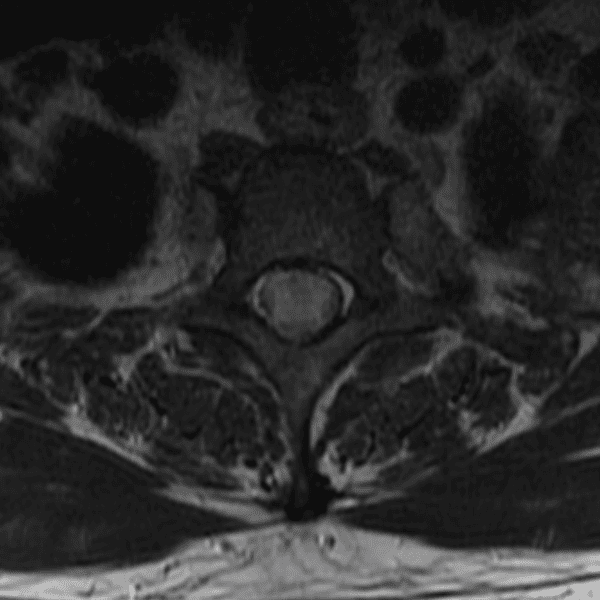

Simulates call by including subtle or difficult cases and some normals.

35 cases